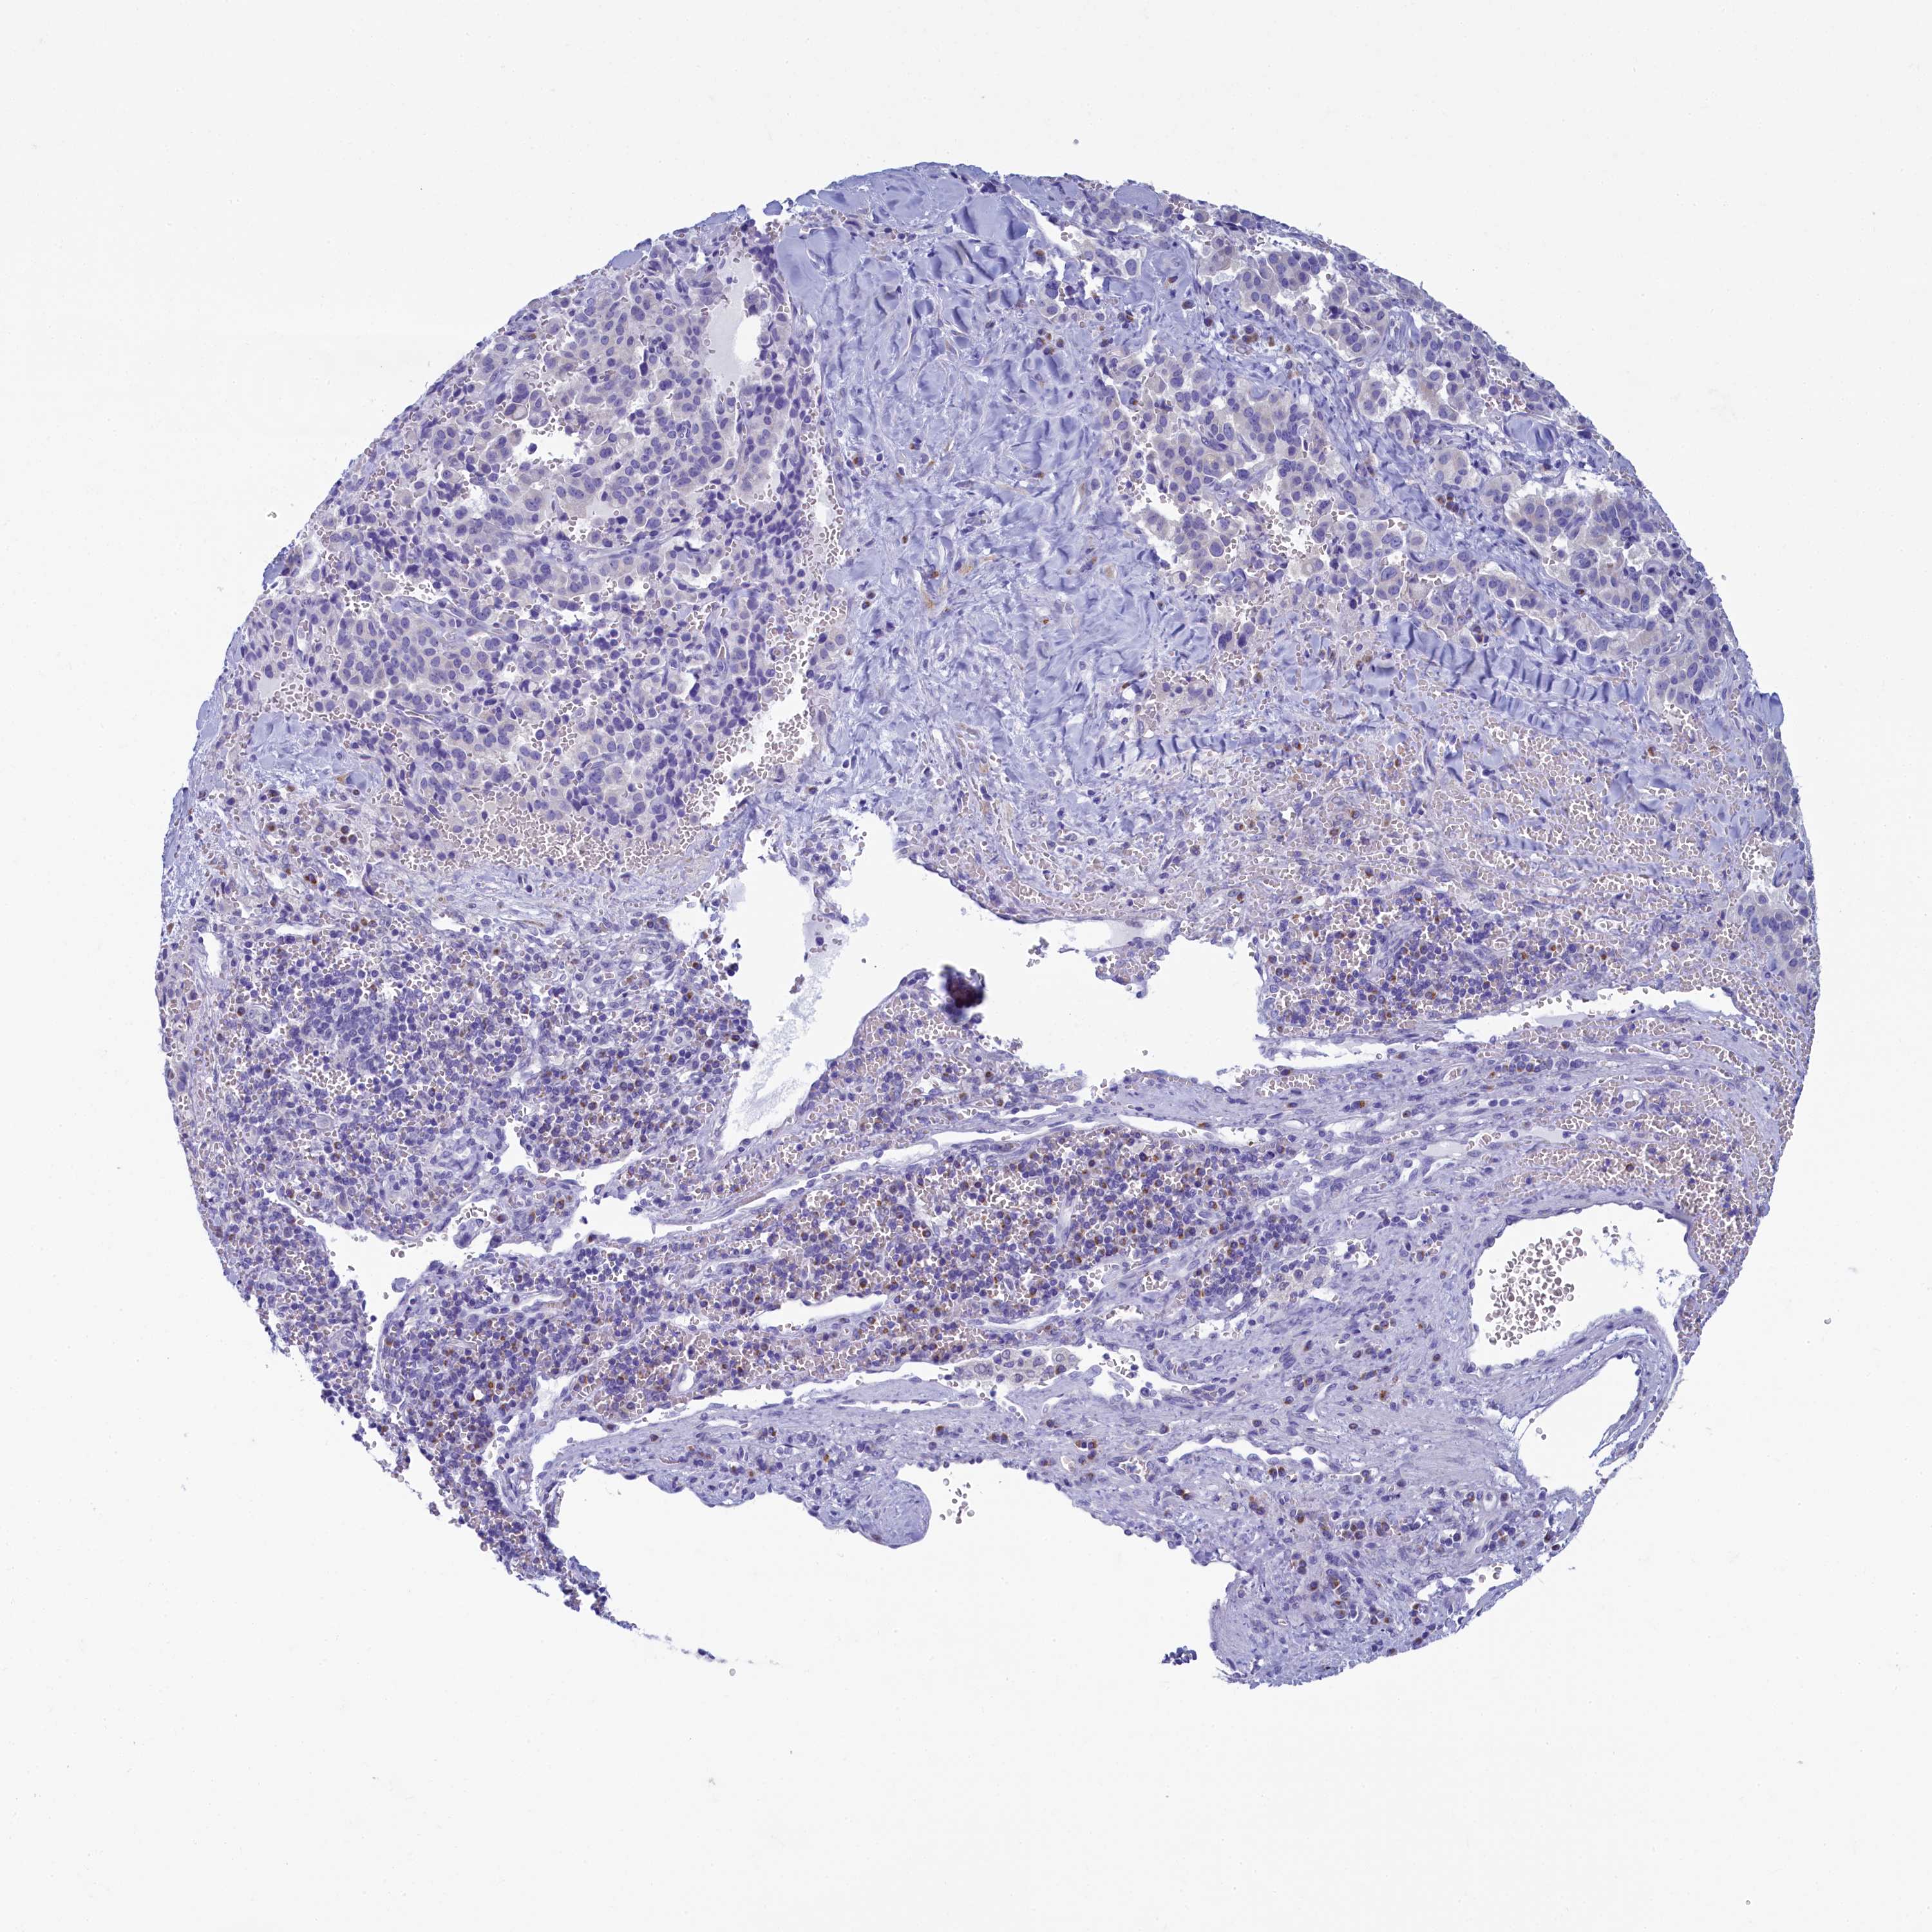

PANCREATIC CANCER - Protein expressioni

A mouse-over function shows sample information and annotation data. Click on an image to view it in a full screen mode. Samples can be filtered based on level of antibody staining by selecting one or several of the following categories: high, medium, low and not detected. The assay and annotation is described here.

Note that samples used for immunohistochemistry by the Human Protein Atlas do not correspond to samples in the TCGA dataset.

Antibody stainingi

Antibody staining in the annotated cell types in the current human tissue is reported as not detected, low, medium, or high, based on conventional immunohistochemistry profiling in selected tissues. This score is based on the combination of the staining intensity and fraction of stained cells.

Each image is clickable and will lead to virtual microscopy that enables deeper exploration of all samples and also displays staining intensity scores, fraction scores and subcellular localization as well as patient and tissue information for each sample.

Antibody HPA039272

Staining

High

Medium

Low

Not detected

Intensity

Strong

Moderate

Weak

Negative

Quantity

>75%

75%-25%

<25%

None

Location

Nuclear

Cytoplasmic/membranous

Cytoplasmic/membranous,nuclear

Adenocarcinoma, NOS